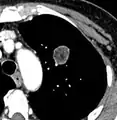

Low attenuating nodule (in this case a fat containing hamartoma).[9]

- Areas of fatty tissue (−40 to −120 HU) indicates a hamartoma. However, only about 50% of hamartomas are fat containing.[9]